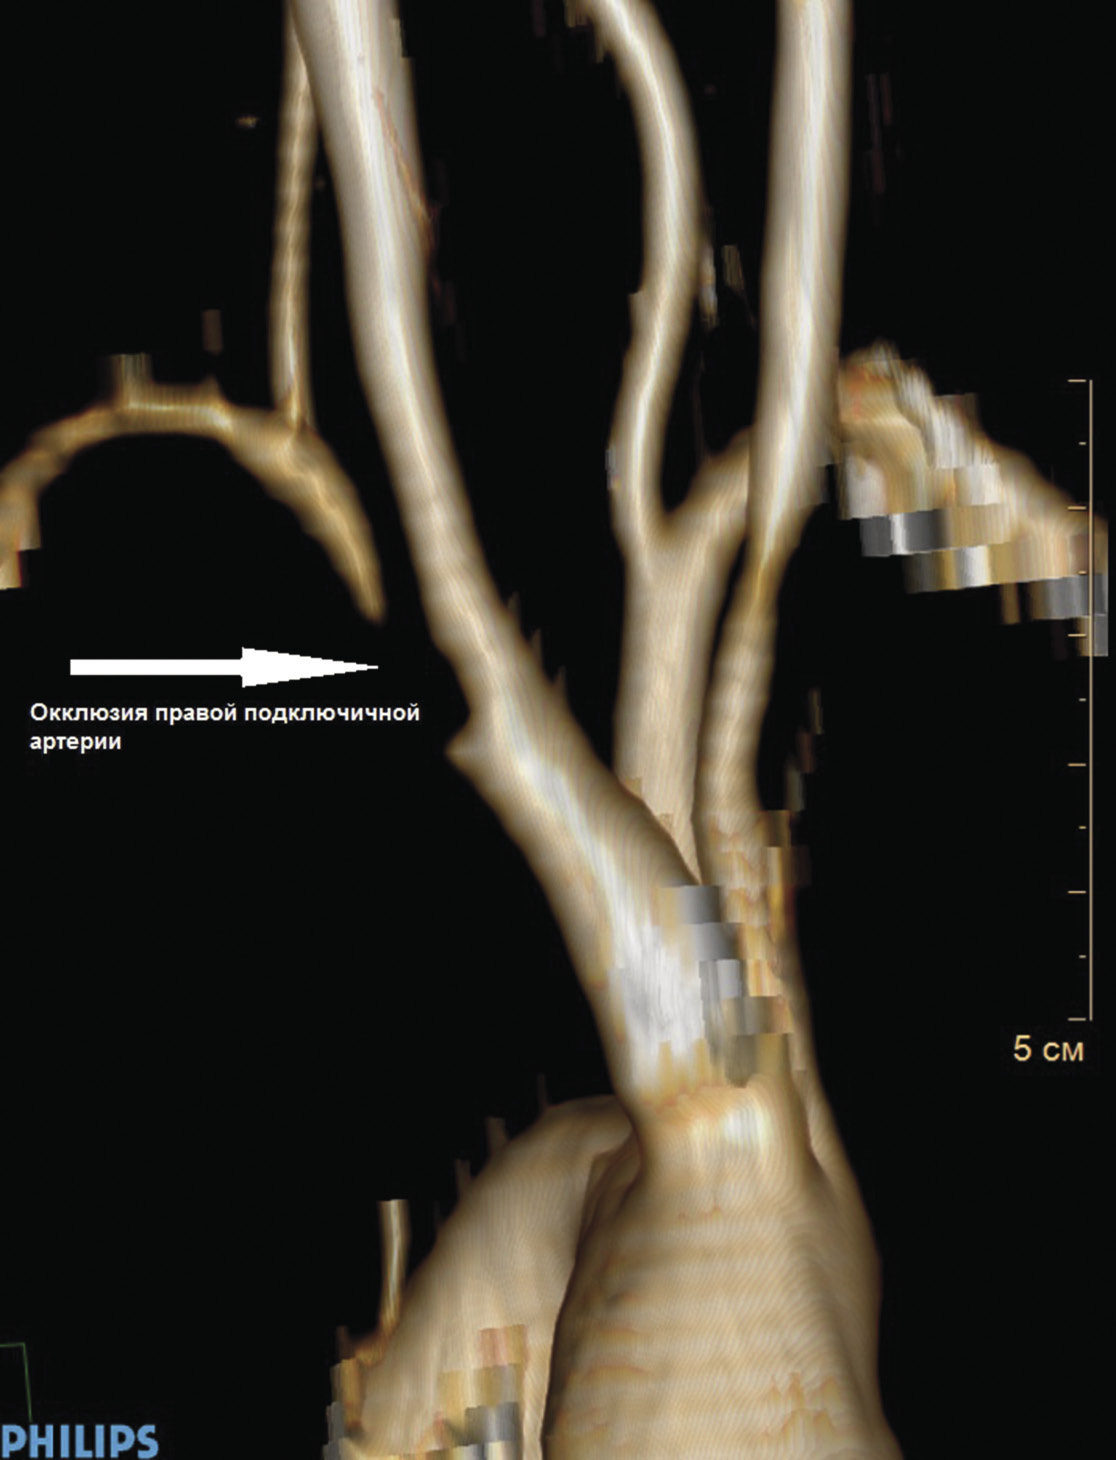

Пациент К., 55 лет, поступил в отделение сосудистой хирургии ФГБУ ФНКЦ ФМБА России 30.08.2017 г. с жалобами на частые головные боли, выраженные головокружения и пошатывания при ходьбе, которые беспокоят в течение 2 лет. Эпизодов острого нарушения мозгового кровообращения (ОНМК) не было. В анамнезе АББШ, неоднократные тромбэктомии и реконструкции дистальных анастомозов с обеих сторон. При физикальном осмотре отсутствует пульсация на ППА, градиент артериального давления на верхней конечности 40 мм рт. ст. При дуплексном сканировании выявлены окклюзия ППА в первом сегменте с ретроградным кровотоком по позвоночной артерии, коллатеральный кровоток по правой плечевой артерии. При КТ с контрастным усилением визуализированы критический стеноз БЦС, окклюзия ППА в первом сегменте без значимых изменений позвоночных и сонных артерий в экстра- и интракраниальных отделах (рис. 1, 2). В связи с наличием клинических проявлений сосудисто-мозговой недостаточности (СМН) на фоне выявленной патологии БЦА были определены показания к оперативному лечению в целях профилактики ОНМК.

Рис. 2. КТ с контрастным усилением: окклюзия правой подключичной артерии в первом сегменте

Задачей оперативного лечения было восстановление магистрального кровотока по БЦС, ППА и антеградного кровотока по правой позвоночной артерии. Эндоваскулярная коррекция стеноза БЦС трансфеморальным доступом признана нецелесообразной в связи с высоким риском осложнений доступа после неоднократных операций в паховых областях.

Хронический характер окклюзии ППА давал мало шансов на успех эндоваскулярной реканализации. Анатомический тип отхождения БЦА от дуги аорты не позволял обеспечить адекватную поддержку проводниковым катетером. Кроме того, эндоваскулярная реканализация хронической окклюзии ППА могла оказаться безуспешной, требовала бы применения стента или эндопротеза, который перекрывал бы устье позвоночной артерии и ОСА. При этом была бы необходимость проксимального смещения второго стента из короткого БЦС в просвет дуги аорты, иначе про-изошли бы наложение и деформация стентов в области бифуркации БЦС.